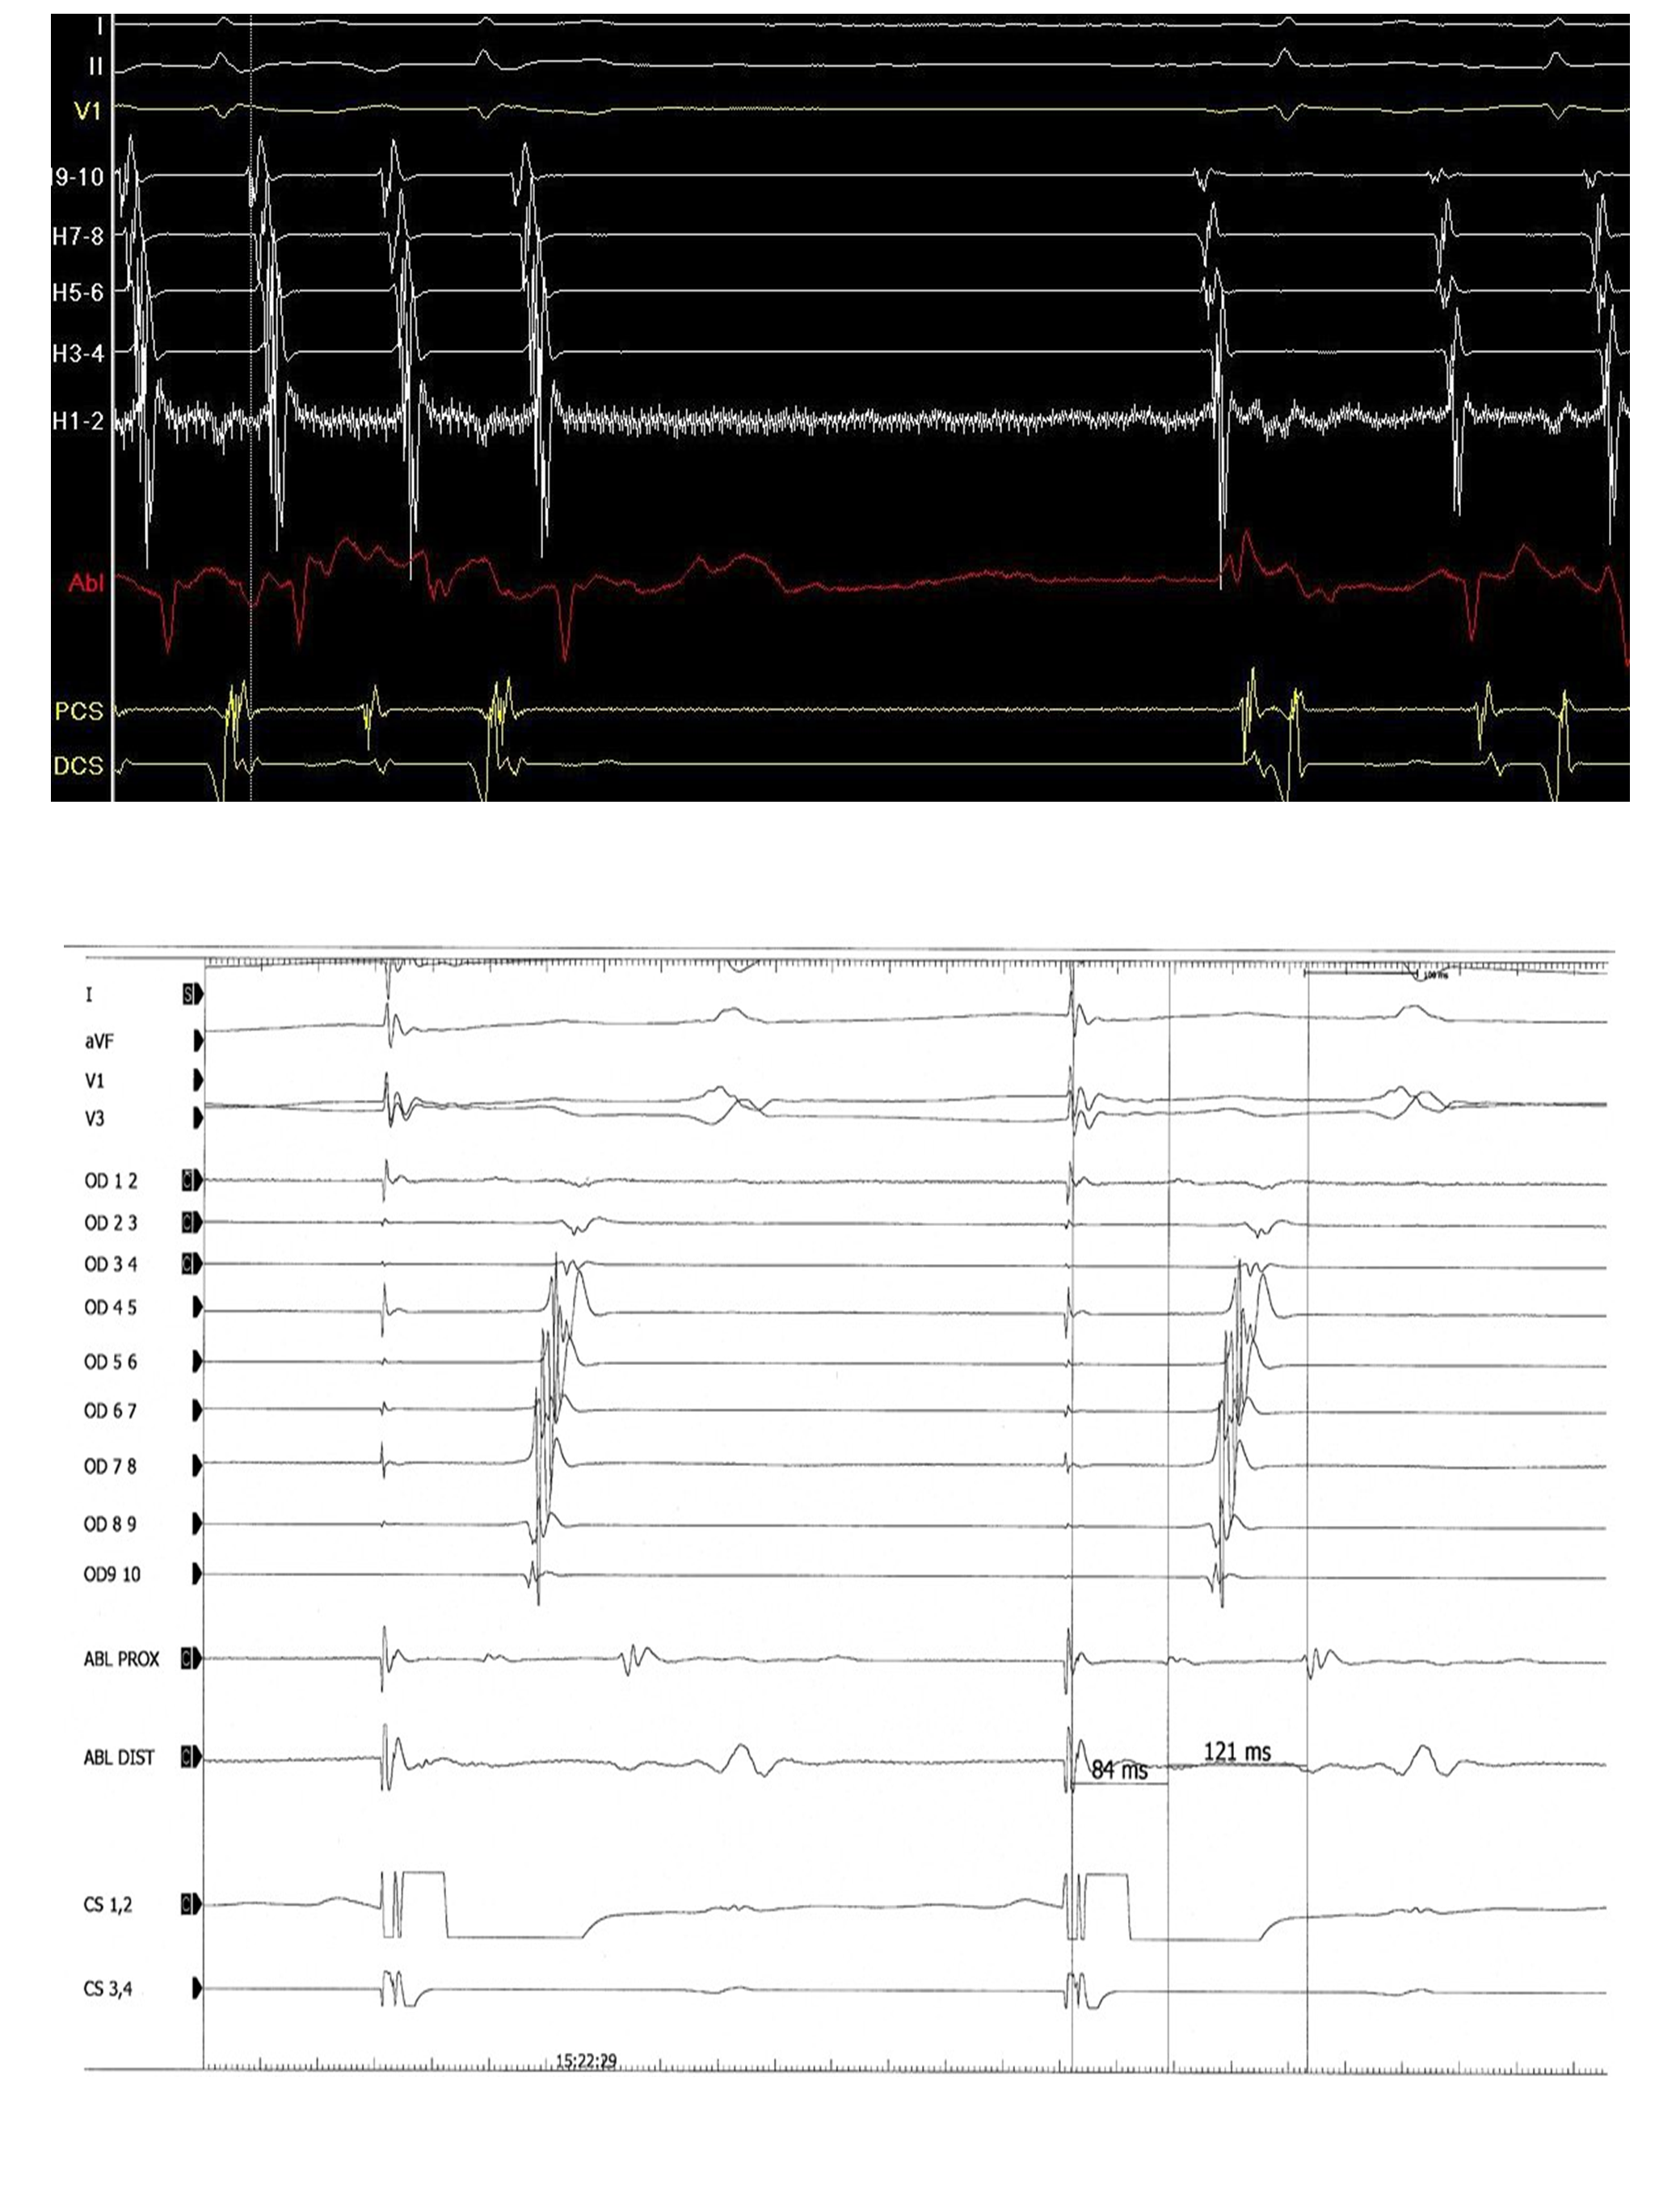

Nous avons réalisé chez certains patients des tirs continus de 240 sec et chez d’autres plusieurs tirs séparés de 120 sec.

Le succès de l’ablation était confirmé par l’obtention d’un bloc bidirectionnel c’est à dire en stimulant le sinus coronaire proximal, l’oreillette droite basse (proximale) se dépolarisait en dernier et en stimulant l’oreillette proximale, le sinus proximal se dépolarisait en dernier. La mise en évidence d’un aspect de double potentiel sur l’ablation était un argument de succès de l’ablation.

Nous avons effectué une ablation par radiofréquence chez tous les patients. Au cours de cette dernière, l’aspect électrocardiographique dominant était celui d’un flutter dans 85% et 15% des patients étaient en rythme sinusal lors de l’ablation. Nous avons obtenu un bloc bidirectionnel dans 95% des procédures et dans 5% un bloc unidirectionnel (Figures 6 et 7). La durée moyenne de la procédure d’ablation par contre a été évaluée dans notre série et elle était de 43 min avec des extrêmes de 35 et 70 min. Nous avons noté un taux de succès de 95%. Chez 5% des patients, un choc électrique externe avait permis de remettre le patient en rythme sinusal.

Figure 6 : Arrêt d’un flutter isthmique droit antihoraire lors de l’ablation d’un des patients

Figure 7 : Aspect de double potentiel en post ablation d’un des patients.